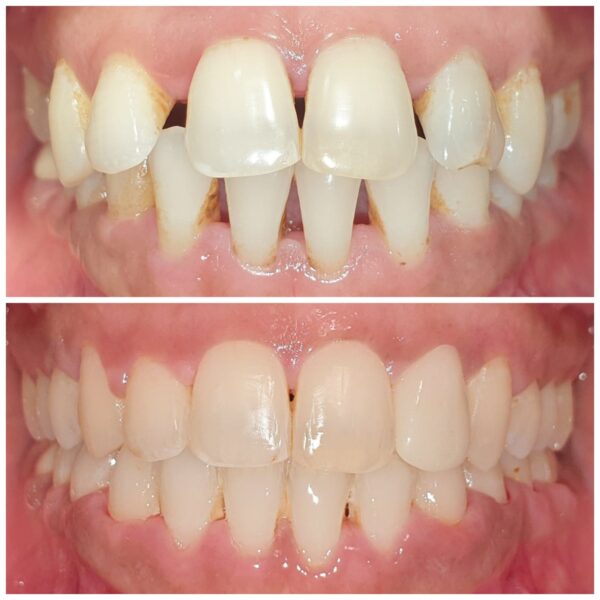

Comprehensive orthodontic management for patients requiring structured smile correction. From diagnosis to active alignment and retention, ensuring predictable and aesthetics outcomes.

Specialized orthodontic care improves alignment accuracy, bite function, smile aesthetics, and long-term stability.